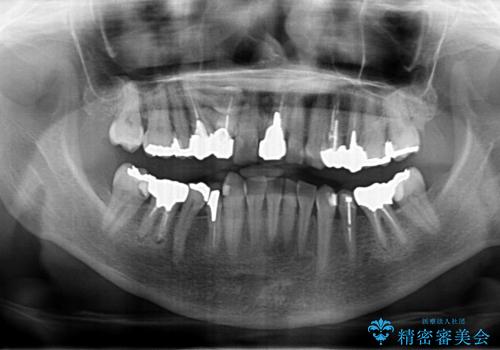

50代女性 銀歯をとって白いつめものに 全体的な治療

- 銀歯や被せ物のやり替えをご希望で来院。悪いところはすべて治していきたいとのことでした。

根の治療を含めてしっかりやり直しを行いました。

本数も多く、時間はかかりましたが、しっかり通いきっていただきました。